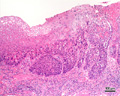

- ★(3)Esophageal carcinoma (squamous cell carcinoma)

Gross appearance: At the mid esophagus, there is a 3x1cm brownish flat lesion (yellow circle). There are similar, smaller lesions which are scattered more proximally (red circle, at left of image). The lesions are made more conspicuous by their lack of iodine staining (at right).